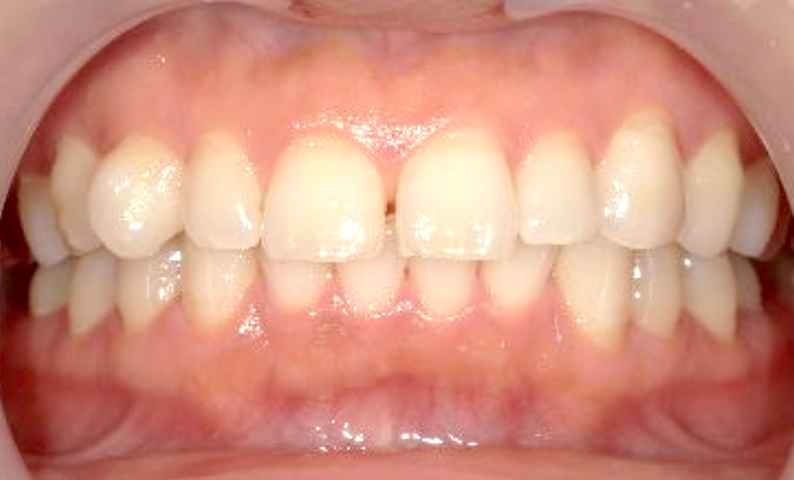

| 治療前 | 治療後 |

|---|---|

|